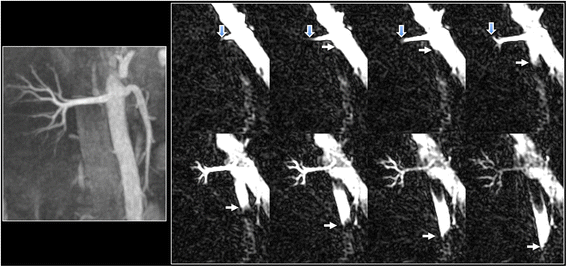

Dynamic flow patterns were well shown in the aorta, coronary and renal arteries using cine FISS ASL (Figs. 4, 5 and 6; see Additional file 1: Figure S4 and S5). The labeled bolus could be reliably visualized in subtracted images over the entire cardiac cycle as it traversed the length of the vessel. In contrast, the bolus could only be reliably visualized over a few cine frames in non-subtracted images (see Additional file 1: Figure S6).

Example of cine FISS ASL for dynamic flow visualization in the right renal artery and abdominal aorta of a healthy subject. Left: maximal intensity projection (MIP) from breath-hold radial QISS acquisition. Right: Oblique coronal cine FISS ASL (eight frames shown out of 32 acquired) using 6-mm slice thickness demonstrates progression of the labeled bolus along the entire main segment of the right renal artery (open arrows) into the small intrarenal branches, as well as progression of the labeled bolus in the aorta (solid arrows)

Semi-projective cine FISS ASL of the renal arteries. Top: 24-mm MIP from breath-hold radial QISS acquisition. Bottom: Axial cine FISS ASL (eight frames shown out of 32 acquired) using 24-mm slice thickness demonstrates symmetrical progression of the labeled bolus through the right and left renal arteries into the intrarenal branches